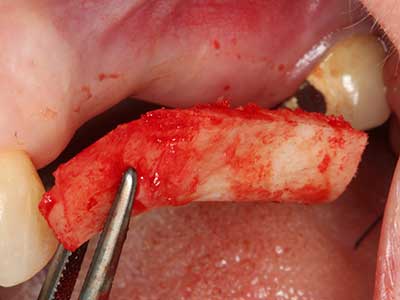

Indikation: Eigenknochengewinnung

Autogene Knochentransplantate finden als Blöcke, Schalen, Ringe und gerade in der Kombination mit Knochenersatzmaterialien als Späne Anwendung. Wird gleichzeitig mit der Augmentation ein Implantatbett aufbereitet, so haben sich zur Sammlung der anfallenden Knochenspäne verschiedene Knochenfiltersysteme bewährt. Alternativ kann eine niedrigtourige Implantatbettpräparation ohne Wasserkühlung erfolgen. Wird kein Implantat inseriert, so lassen sich mit Bone Scrapern Knochenspäne aus der Peripherie gewinnen. Ebensolches ist auch mit speziellen Ansätzen mittels Piezochirurgie möglich, wobei sich in einer eigenen Studie im direkten Vergleich zu mit Rosenbohrern gewonnenen Spänen eine bessere Qualität für die Piezospäne nachweisen ließ (Chiriac, Herten et al. 2005).

Bei der Knochenblockentnahme zeigen sich weitere Vorteile für die Piezochirurgie: Neben der bereits beschriebenen hohen Präzision bei der Osteotomie stellt sich gerade die Verwendung der dünnen Sägespitzen als besonders materialschonend heraus. Bei der Verwendung insbesondere von Lindemannfräsen sind mit deutlich höheren Entnahmeverlusten durch die dickere Instrumentenspitze zu rechnen (Lakshmiganthan, Gokulanathan et al. 2012). Die insbesondere bei retromolar entnommenen Blocktransplantaten notwendige basale Abtrennung wird durch speziell hierfür vorgesehene rechtwinklige Sägen erleichtert, so dass die Piezochirurgie als präzises, übersichtliches und sicheres Verfahren zur retromolaren Knochenblockgewinnung angesehen wird (Happe 2007) (Abb. 1-12).